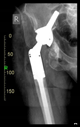

The guiding wire was inserted and controlled with fluoroscopy flashes (Figure 4). The drilling and reaming were carried out in accordance with the recommendations:

Figure 4.

The biocompatible aiming device after insertion of the guiding wire.

The direction of the cup stem was determined by the guide wire. The aiming device was needed to introduce this wire. After removing the aiming device, the next step was the drilling. Since a cannulated drill bit was used, the previously installed wire could guide the process. A self-positioning reaming tool was then used in the drilled channel. In the prepared cavity, the cup was fitted perfectly. Of the two stemmed cups available to us, the McMinn cup (Waldemar Link, Hamburg, Germany) had the simpler geometry and was therefore chosen. The stemmed cup was inserted according to the manufacturer’s recommendation. In the presence of a significant bone defect, a synthetic bone graft may be impacted for substitution.

The radiological examination allowed us to verify the close bone-to-implant contact and the unchanged position of the implant during follow-up.

In all the cases operated with the above-described targeting procedure, the stems of the cups remained between the cortical bone surfaces without perforation of the linea terminalis, as shown by postoperative radiographs. There were no complicated surgical situations. In 16 cases, the wound healings were uneventful, and the hips were able to bear weight again after postoperative rehabilitation.